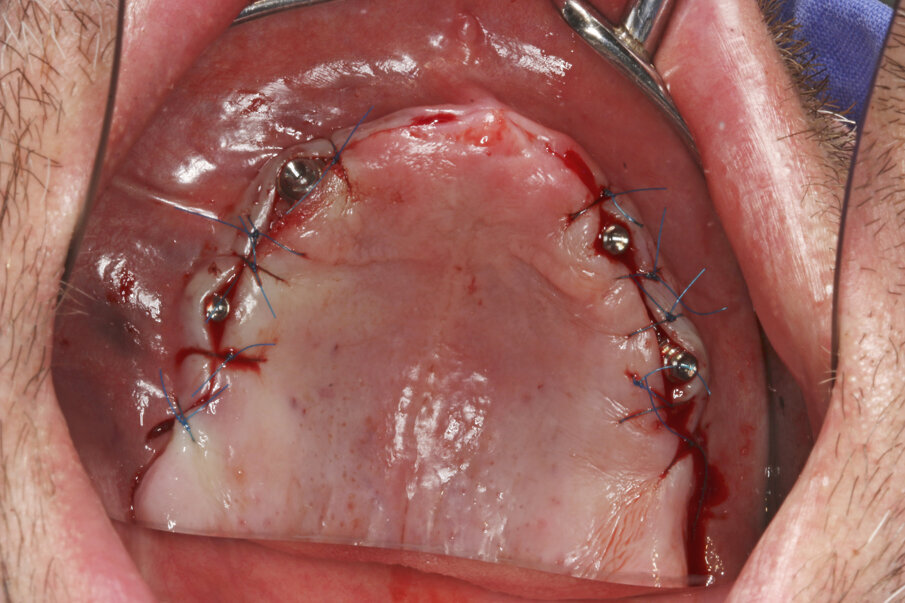

Prior to surgery, intra-oral scans of the edentulous upper jaw and dentate lower jaw were performed. The existing denture was used first as a surgical guide and then as a provisional prosthesis, after removing the palate (Fig. 4). Immediately after implant placement (Figs. 5–10), abutment position was registered with an intra-oral scan (Fig. 11). The provisional prosthesis was prepared fromthe existing denture (Figs. 12 & 13) and then the Atlantis BridgeBase was designed (Fig. 14).

Fig. 7: Multibase abutments inserted for immediate loading.

Fig. 8: The abutments were torqued to 25 Ncm.